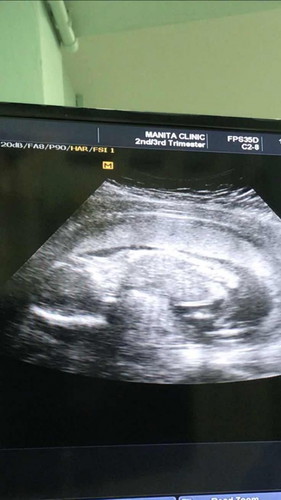

18wks รับบทเปนเด็กขี้อายไปแล้ว1

ไม่ยอมให้เหนเลยว่าจู๋หรือจิ้ม นอนคว่ำอย่างสบายใจ เดือนหน้ารอลุ้นใหม่